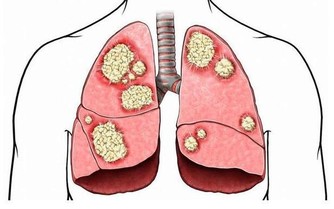

發霉食品中的黃曲霉毒素為致肝癌物質,致癌所需時間最短僅為24週,

因此食物應妥為存放,一旦發霉就應立即丟棄,

尤其是黃豆、花生、紅薯、甘蔗等,切不可再食用。

2、菸酒

煙中含有的尼古丁和酒的代謝產物乙醇對肝臟來說極其不利,是導致疾病、誘發癌症的主要危險因素之一。

非必要場合盡量不要接觸。